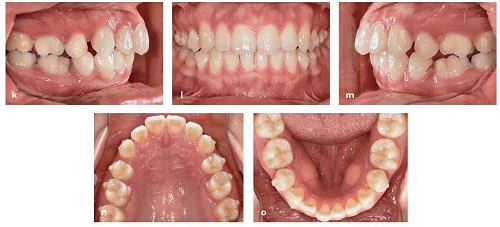

Một bệnh nhân nữ 17 tuổi có sai khớp cắn loại II với sự nhô ra của hàm trên và hàm dưới và chen chúc nhẹ (Hình 13-16a đến 13-16j).

Hồ sơ trước xử lý. Bệnh nhân có một sai khớp cắn loại II với hàm trên và hàm dưới nhô trước và chen chúc ít

Tại tháng 14 trên giao thức thay đổi khay 2 tuần một lần, khoảng nhổ răng đã được đóng (Hình 13-16k đến 13-16o).

Hồ sơ tiến độ tại tháng 14 với khoảng nhổ răng được đóng lại. Một số tipping phía gần của răng hàm lớn thứ nhất được thấy. (p) Tiến hành chụp phim toàn cảnh panorama cho thấy các răng hàm lớn thứ nhất đã tipping về phía gần vào vị trí nhổ răng.